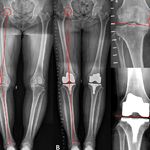

(شکسته بندی،دردمفصلی استخوانی،دنبلیچه،ناف،خارپاشنه،حجامت،رگ گیری،سیاتیک،دیسک کمر گردن،دست وپا،فک،بینی،گیزگیزشدن بدن،واریس،روماتیسم،زخم بستر..)

شکسته بندی حرفه ای،دررفتگی تمامی نقاط بدن و تمامی اعضاء.درمان دیسک کمر،گردن.درمان سیاتیک،رگ گیری اصولی وحرفه ای.حجامت،بادکش،ناف،دنبلیچه،سق دهان،خارپاشنه،تول،ترس،کجی استخوان،ترقوه،کتف،لگن،گردن، تشخیص و درمان دردهای مفصلی و اسنخوانی..گیزگیز کردن و خواب رفتگی اعضاء بدن.درمان تضمینی دردهای کمری.مشاوره و درمان ضایعاتی که بصورت غده های چربی،عفونی،استخوانی دربدن نمایان میشوند. مشاوره و درمان زخم بستر،وزخمهای عفونی،سوزش،خارش،بیماریهای پوستی و بیماریهای دیگر.... ( اعزام به منزل ،بیمارستان جهت بیمارهای اورژانسی،مسن. ) جهت اطلاعات بیشتر،دریافت نوبت میتوانیدهمین الان باما تماس حاصل نمایید.